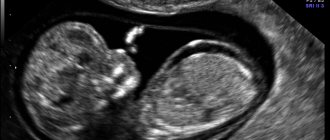

Информативным методом диагностики считается скрининг 1 триместра. Его проводят в 12 недель. Он состоит из УЗИ обследования и анализа крови.

Результаты УЗИ

В процессе УЗИ оценивают строение будущего человека. При ХА обнаруживают соответствующие признаки. Ими являются:

• длина носовой кости;

• строение внутренних органов (особенно мочевыделительной системы);

• толщина воротникового пространства.

При наличии нарушений визуально заметны задержки в развитии эмбриона. Это сопровождается дисфункцией кровотока и плаценты.